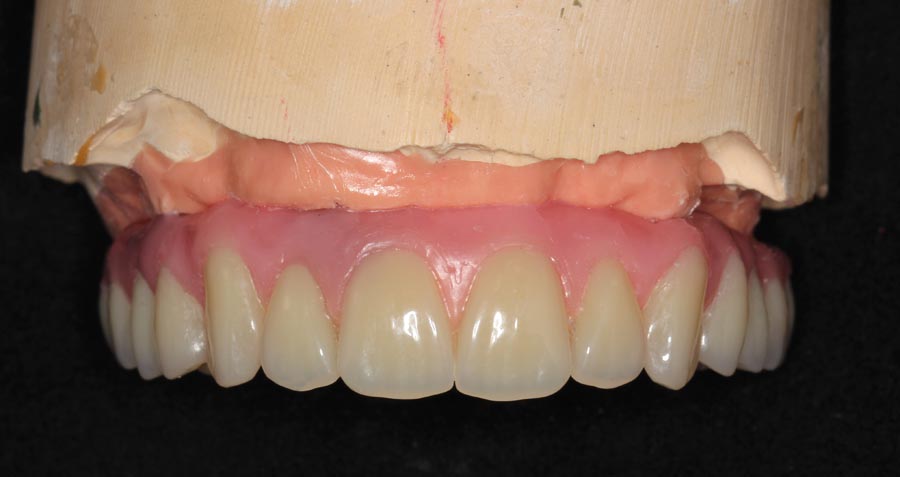

Wax try-in of upper final prosthesis. Nothing is left to chance, we try this in for evaluation of aesthetics, bite, smile and patient approval.

Matching of the gum tissue color is one more step we take in the “customization” process. Most offices have only two choices for the gum color.